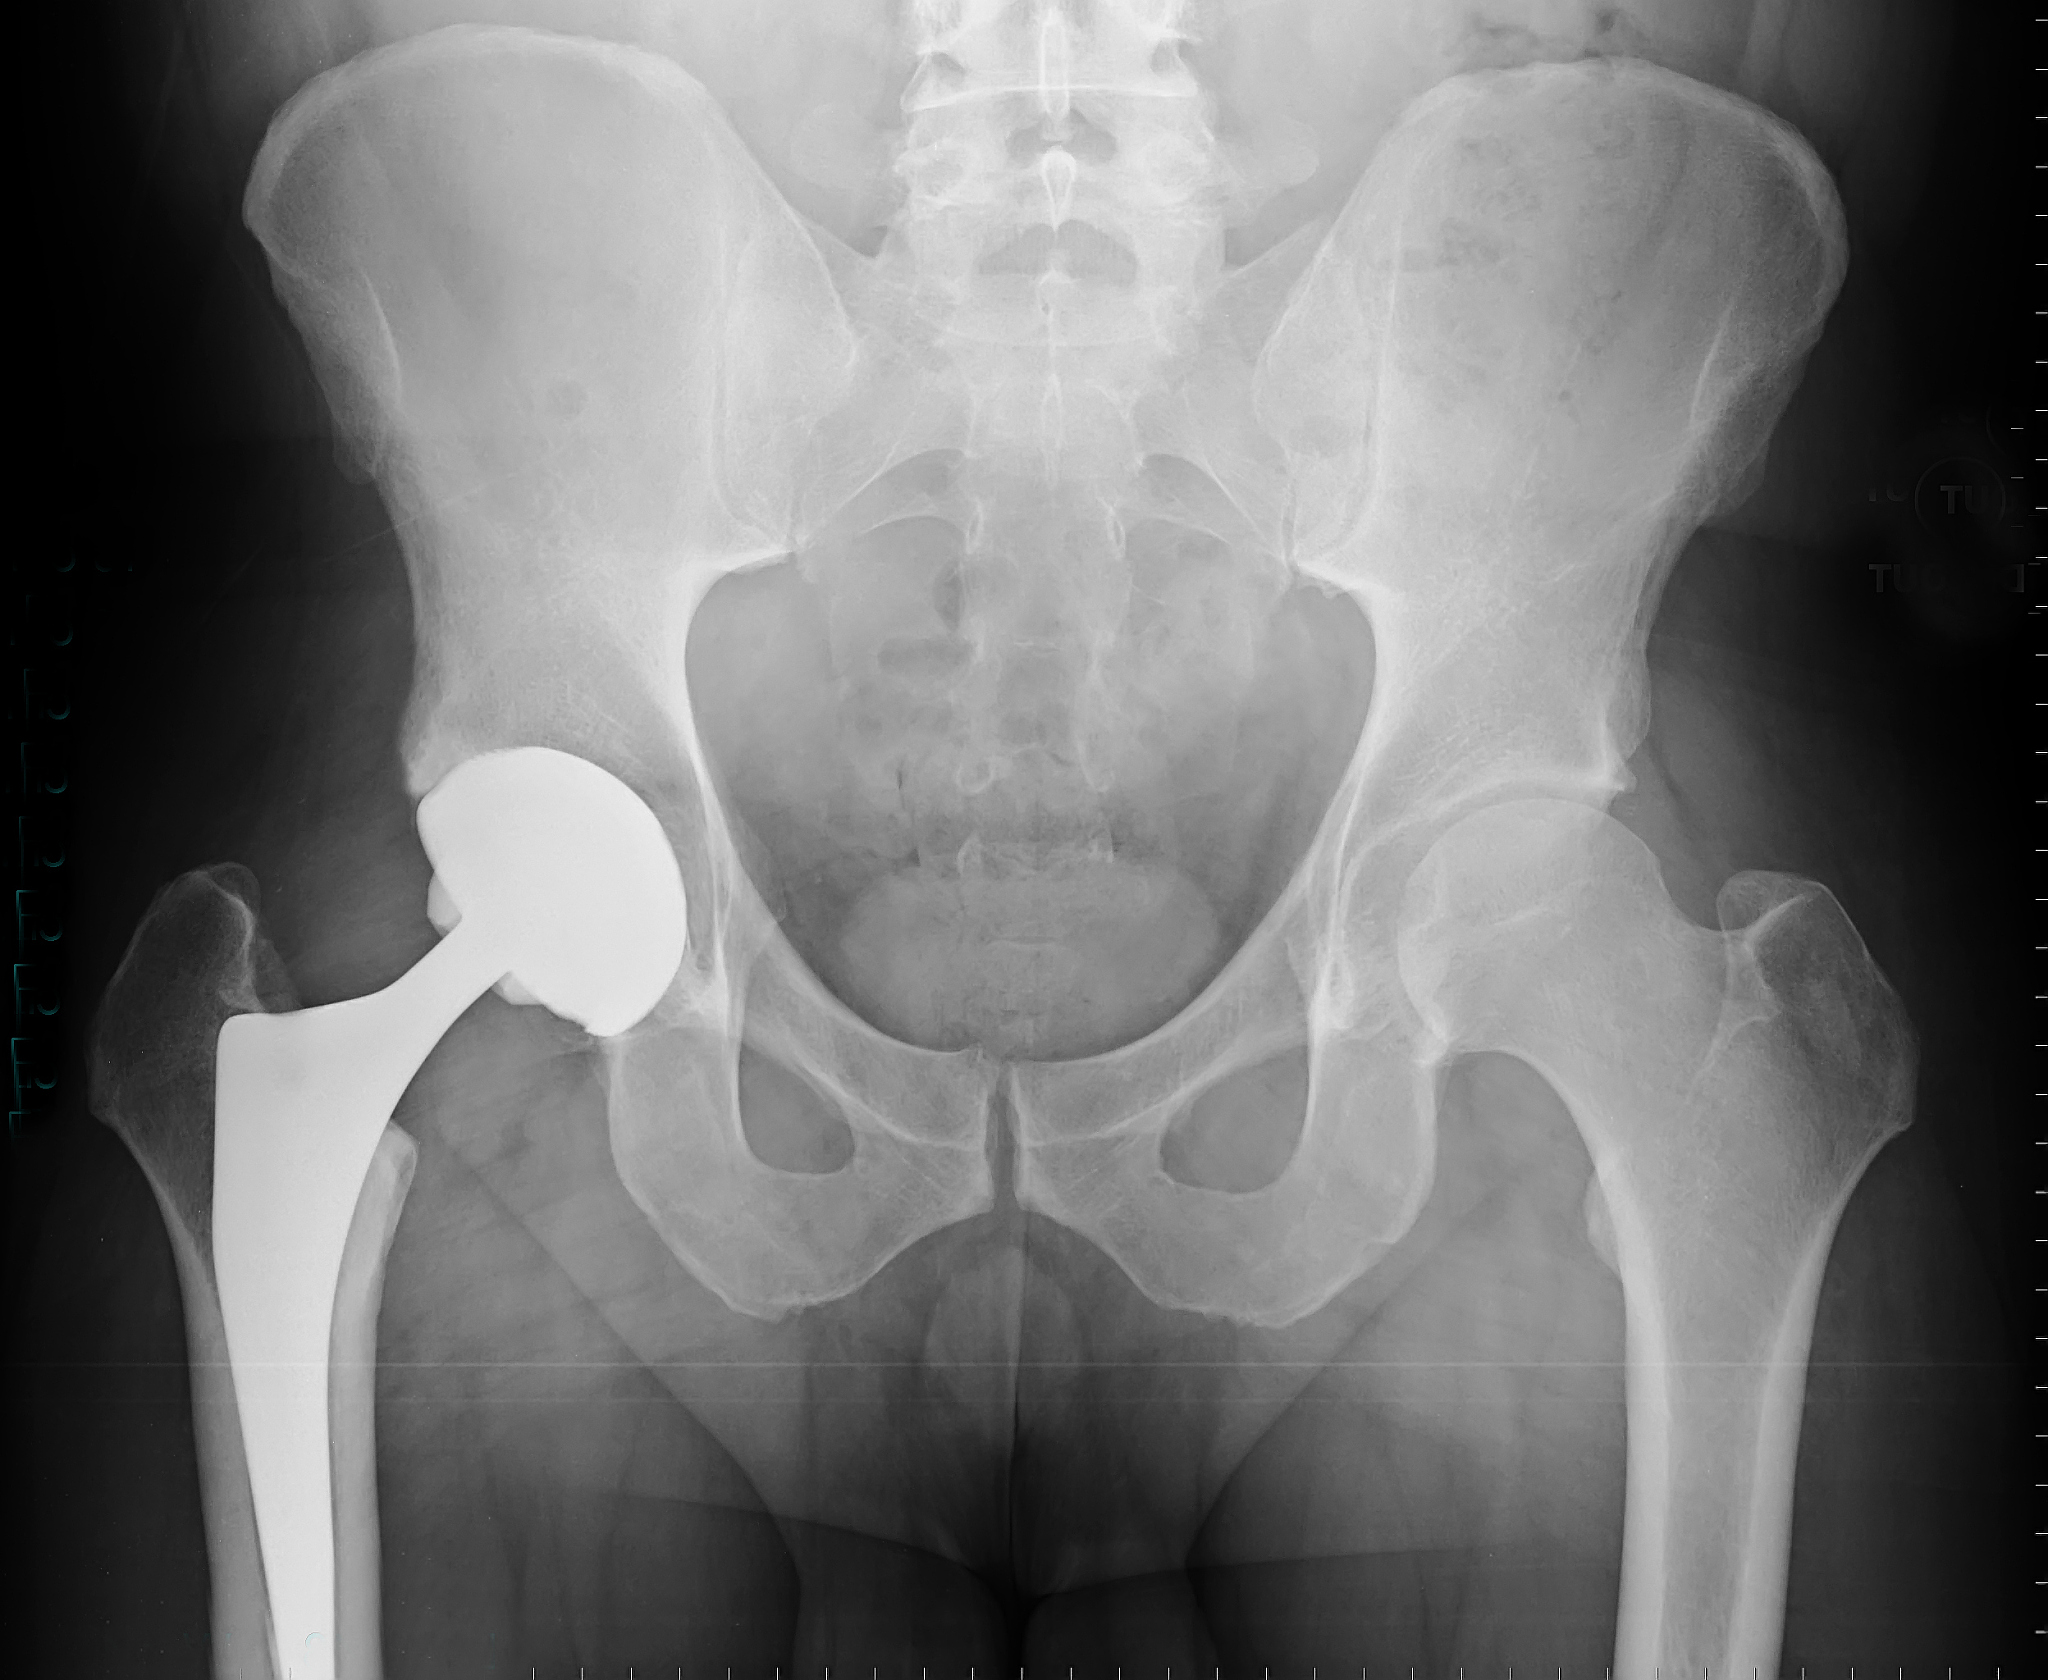

股骨头置换手术是一种治疗股骨头缺血性坏死、骨关节炎、骨折等疾病的手术。该手术通常使用人工髋关节来取代受损的股骨头和髋臼,以恢复关节的正常功能和减轻疼痛。

股骨头置换手术